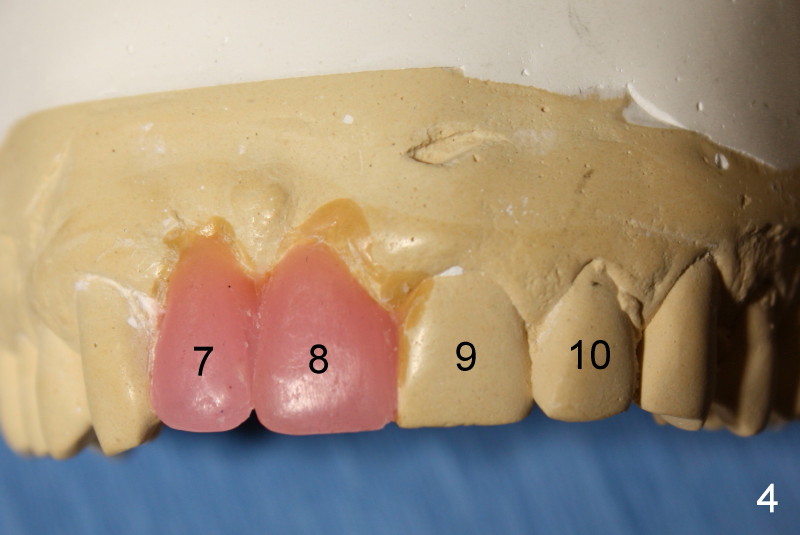

Forty-five-year-old Spanish man has lost the teeth #7 and 8 for 2 years (due to caries, Fig.1,2) with localized buccal plate atrophy (Fig.1-3 *).  Wax-up (Fig.4) shows that implant supported crowns will look longer than their counterparts (#7,8 vs. 9,10).